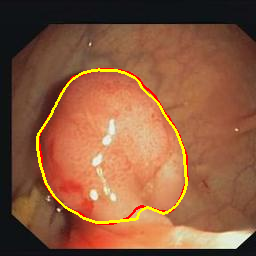

Medical image segmentation is a primary task in many applications, and the accuracy of the segmentation is a necessity. Recently, many deep learning networks derived from U-Net have been extensively used and have achieved notable results. To further improve and refine the performance of U-Net, parallel decoders along with mask prediction decoder have been carried out and have shown significant improvement with additional advantages. In our work, we utilize the advantages of using a combination of contour and distance map as regularizers. In turn, we propose a novel architecture Psi-Net with a single encoder and three parallel decoders, one decoder to learn the mask and other two to learn the auxiliary tasks of contour detection and distance map estimation. The learning of these auxiliary tasks helps in capturing the shape and boundary. We also propose a new joint loss function for the proposed architecture. The loss function consists of a weighted combination of Negative likelihood and Mean Square Error loss. We have used two publicly available datasets: 1) Origa dataset for the task of optic cup and disc segmentation and 2) Endovis segment dataset for the task of polyp segmentation to evaluate our model. We have conducted extensive experiments using our network to show our model gives better results in terms of segmentation, boundary and shape metrics.